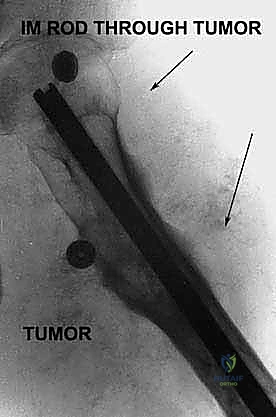

1. أورام العظام والأنسجة الرخوة الخبيثة (Sarcomas)

تُعد الأورام الخبيثة السبب الأكثر شيوعاً. وتشمل الساركوما العظمية (Osteosarcoma)، الساركوما الغضروفية (Chondrosarcoma)، وساركوما إوينغ (Ewing's Sarcoma). عندما يغزو الورم عظام الحوض، أو يحيط بالأوعية الدموية الرئيسية (الشريان والوريد الحرقفي) أو العصب الوركي، يصبح استئصال الورم مع الحفاظ على الطرف مستحيلاً.

2. الإصابات الرضية الشديدة (Severe Trauma)

حوادث السير المروعة، أو الإصابات الناتجة عن الحروب والانفجارات، أو حوادث السحق (Crush Injuries) التي تؤدي إلى تدمير كامل لا يمكن إصلاحه لعظام الحوض والأوعية الدموية المغذية للطرف السفلي. في هذه الحالات، يكون البتر ضرورياً لمنع الغرغرينا والتسمم الدموي القاتل.

إذا أظهرت الفحوصات أن الورم يحيط بالعصب الوركي أو الشريان الحرقفي، فإن محاولة إنقاذ الطرف ستؤدي إما إلى ترك خلايا سرطانية (مما يعني عودة الورم والموت الأكيد)، أو ترك طرف مشلول وغير مفيد وعرضة للعدوى. هنا، يتخذ الدكتور هطيف القرار الطبي الصادق والأمين بضرورة البتر.